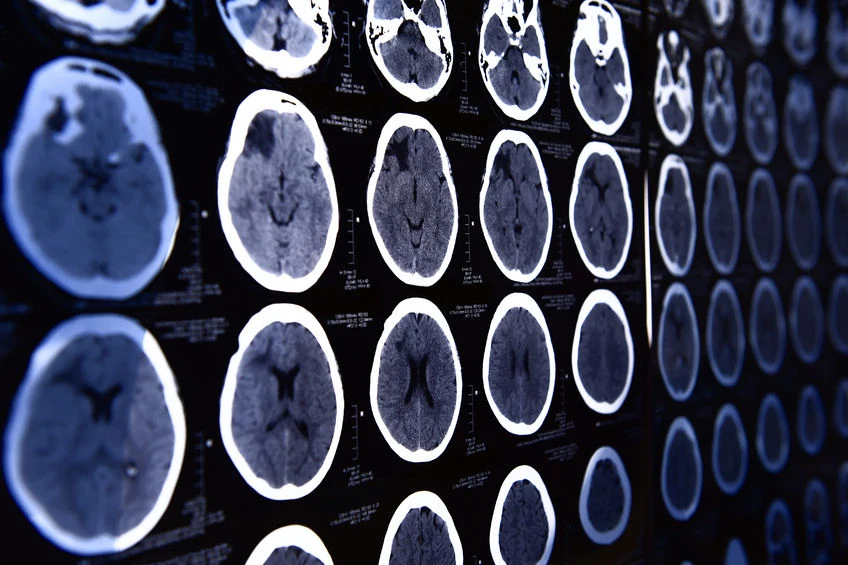

Udało się wyłączyć w mózgu odczuwanie bólu

Naukowcy odkryli niezwykłą metodę blokowania receptorów bólowych, która może doprowadzić do przełomu w medycynie.

Zespół uczonych z Saint Louis University w Missouri zaobserwował, że wystarczy włączyć receptor adenozynowy A3, by uśmierzyć ból w mózgu i rdzeniu kręgowym. Badania przeprowadzone przez Daniela Salveminiego na myszach wykazały, że podobny mechanizm zachodzi najprawdopodobniej u ludzi.Eksperymenty Salveminiego wykazały, że nowo opracowana metoda jest nie tylko skuteczna, ale posiada właściwości przeciwzapalne i przeciwnowotworowe oraz jest nieszkodliwa dla organizmu.Zanim zostaną przeprowadzone jakiekolwiek badania z wykorzystaniem tkanek ludzkich, konieczna jest dodatkowa seria eksperymentów na zwierzętach.